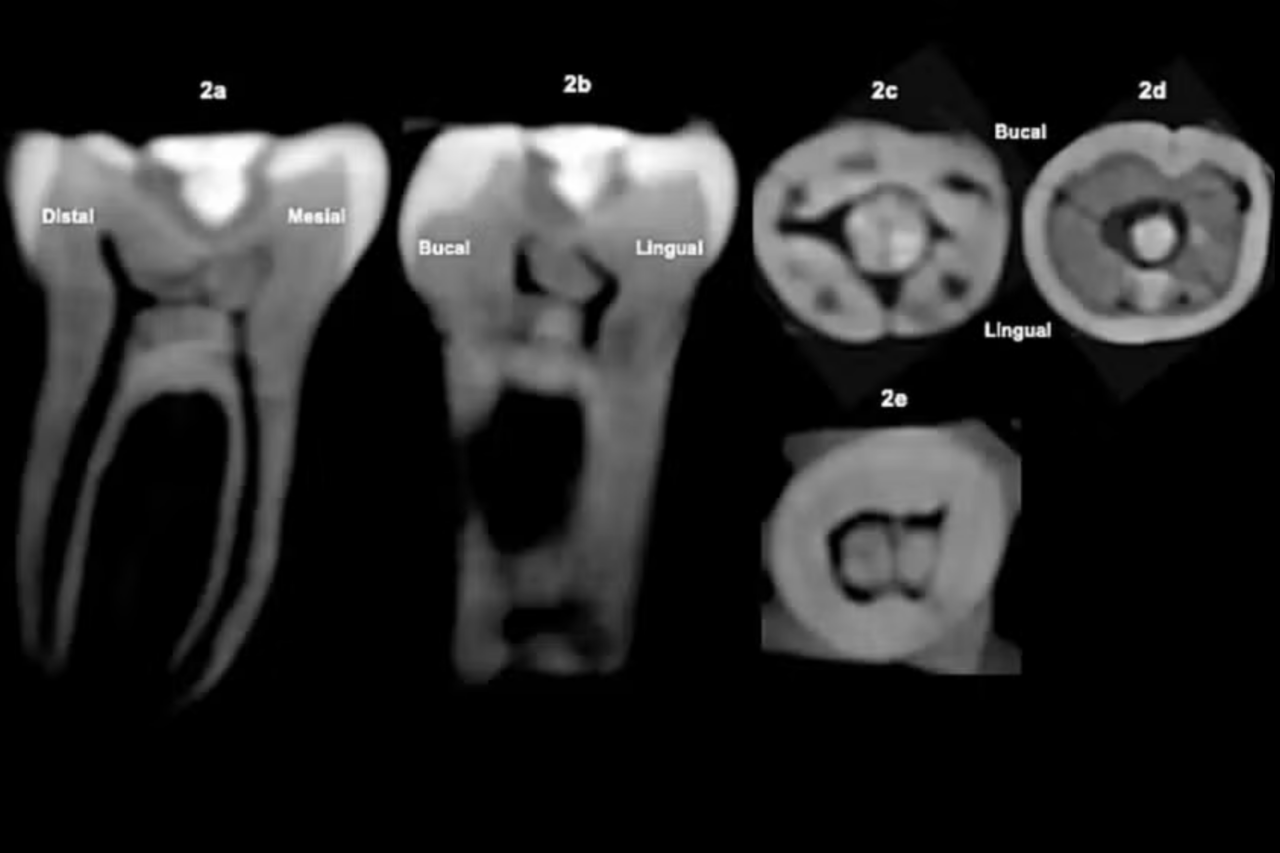

O estudo, publicado na Journal of Archaeological Science: Reports, aponta que esse é o primeiro caso documentado desse tipo de intervenção em um molar entre os maias. A posição da pedra, alinhada com a superfície de mastigação, indica cuidado técnico e conhecimento preciso da anatomia dental.

Exames por tomografia revelaram alterações internas no dente compatíveis com reações biológicas em tecido vivo, sugerindo que o procedimento foi realizado enquanto o indivíduo ainda estava vivo. Esse dado reforça a hipótese de que não se tratava apenas de uma modificação estética.